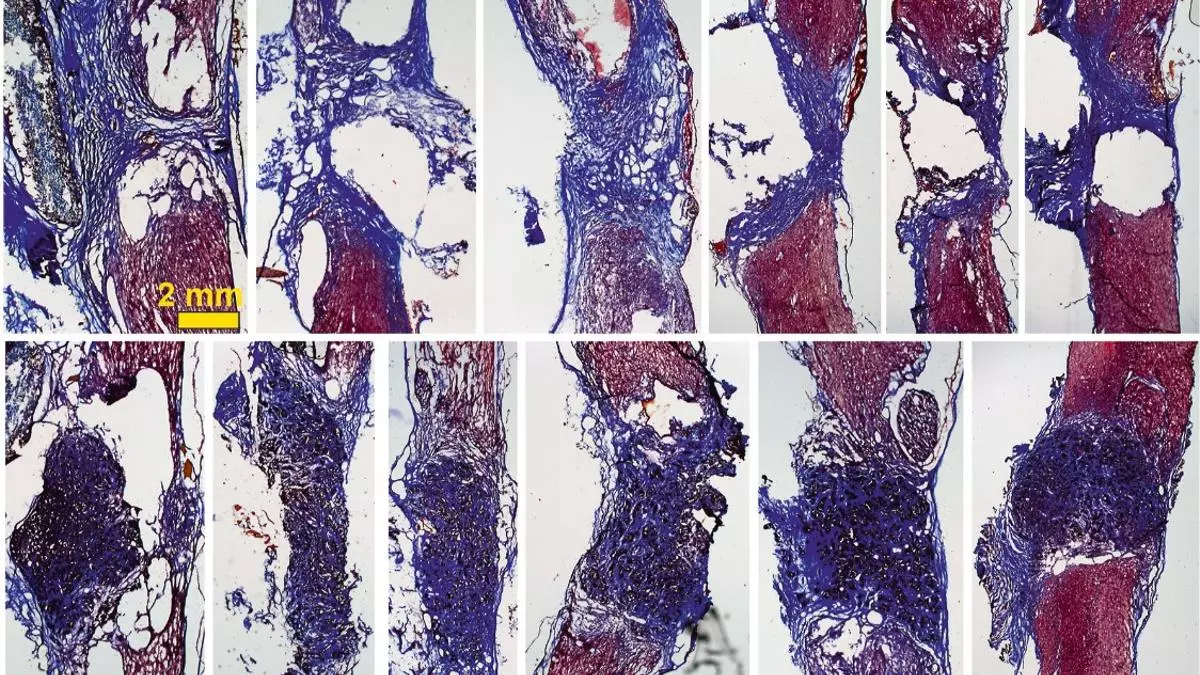

Los tejidos de nuevo crecimiento ‘colonizan’ el espacio de la lesión en la médula espinal gracias a la espuma. / HNP

De esta manera, cuando se coloca el 'scaffold' en la médula espinal --en este caso en un modelo de rata con la médula espinal completamente seccionada a nivel torácico--, los investigadores han visto "que aparecen gran cantidad de vasos sanguíneos, que son fundamentales para nutrir el nuevo tejido, y neuritas (los filamentos que unen unas neuronas con otras)".

La investigadora explica que con esto observan "cómo las neuronas que han sobrevivido en la zona alrededor de la lesión proyectan sus prolongaciones a través del 'scaffold' y lo invaden en toda su extensión 3D". Todo esto, además, mejora con el tiempo: los resultados son incipientes tras 10 días de implante, pero son mucho más evidentes a los cuatro meses.

"Nuestros 'scaffolds' de óxido de grafeno reducido favorecen el crecimiento de vasos sanguíneos más abundantes y más grandes, y neuritas más abundantes, más largas y, además, distribuidas de manera más homogénea en el espacio de la lesión", explica Serrano.